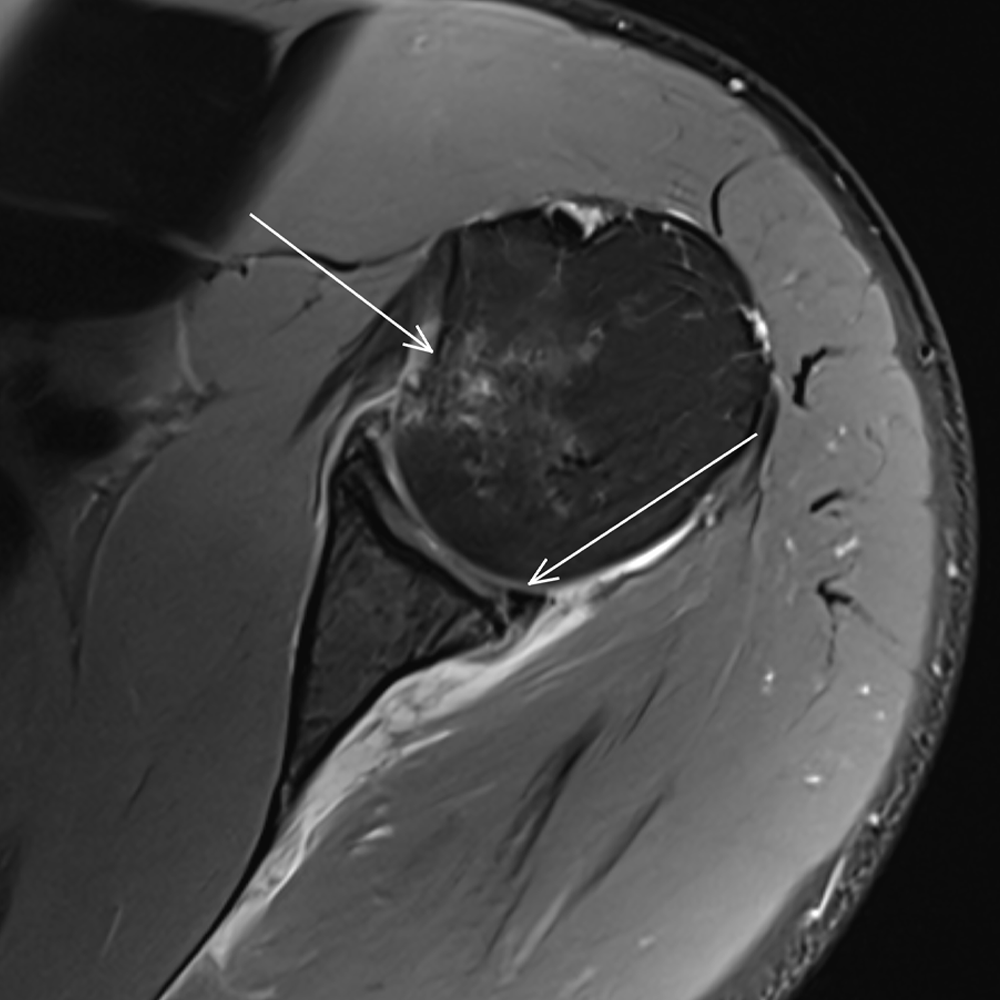

Die MR-Arthrografie ist eine spezielle MRT, bei der zuvor unter CT-Kontrolle ein Kontrastmittel ins Gelenk gespritzt wird, um feine Strukturen und Risse in der anschließenden MRT-Untersuchung besser sichtbar zu machen

MRT des Bewegungsapparates

Die MSK-Bildgebung umfasst Untersuchungen von Muskeln, Sehnen, Bänder, Gelenken und Knochen, um Verletzungen und Verschleißerkrankungen dieser Strukturen präzise zu erkennen.